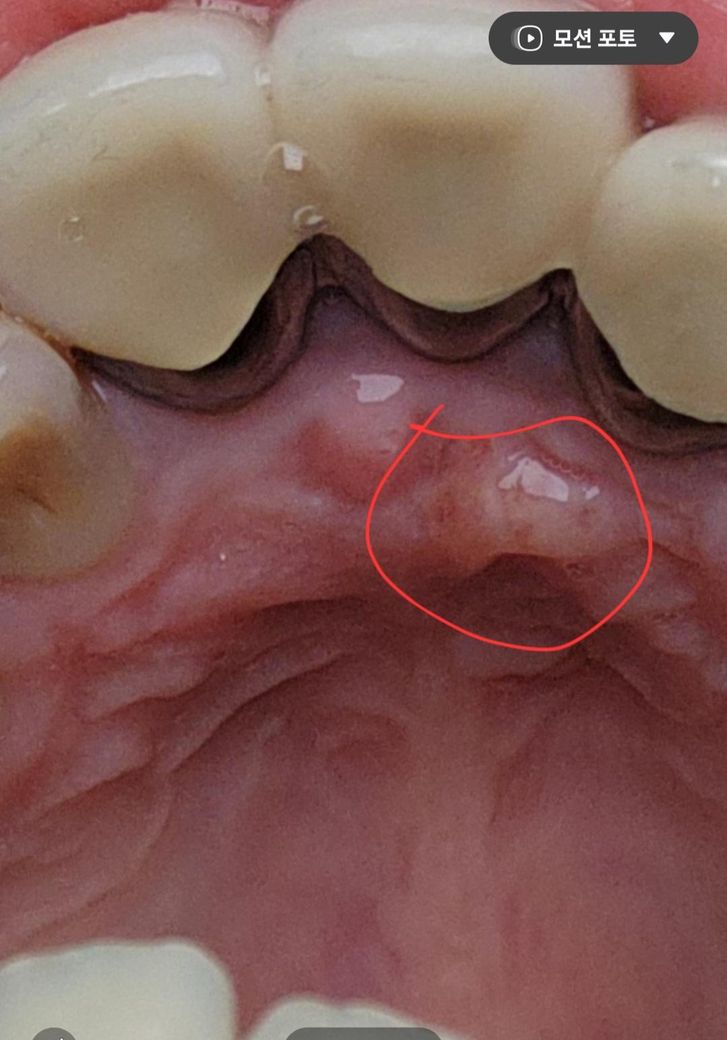

잇몸 입천장쪽에 생긴 이것은 무엇일까요~?

잇몸 입천장쪽에 생긴 이런게 생겼습니다.

생긴지는 한달정도 된것 같은데 혹시 무엇일까요~?

• 3번 째 사진

입천장이 자극을 받아서 생긴 염증일수도 잇지만 치아때문에 생긴 염증일수도 잇으니 치과에 가셔서 일단 치과에 가셔서 엑스레이를 찍어보시는게 좋을것같습니다

사진상 농양이 생긴 것으로 보입니다. 씌운 치아가 신경치료가 되어 있다면 재신경치료, 신경치료가 안되어 있다면 신경치료가 필요할 수 있겠습니다